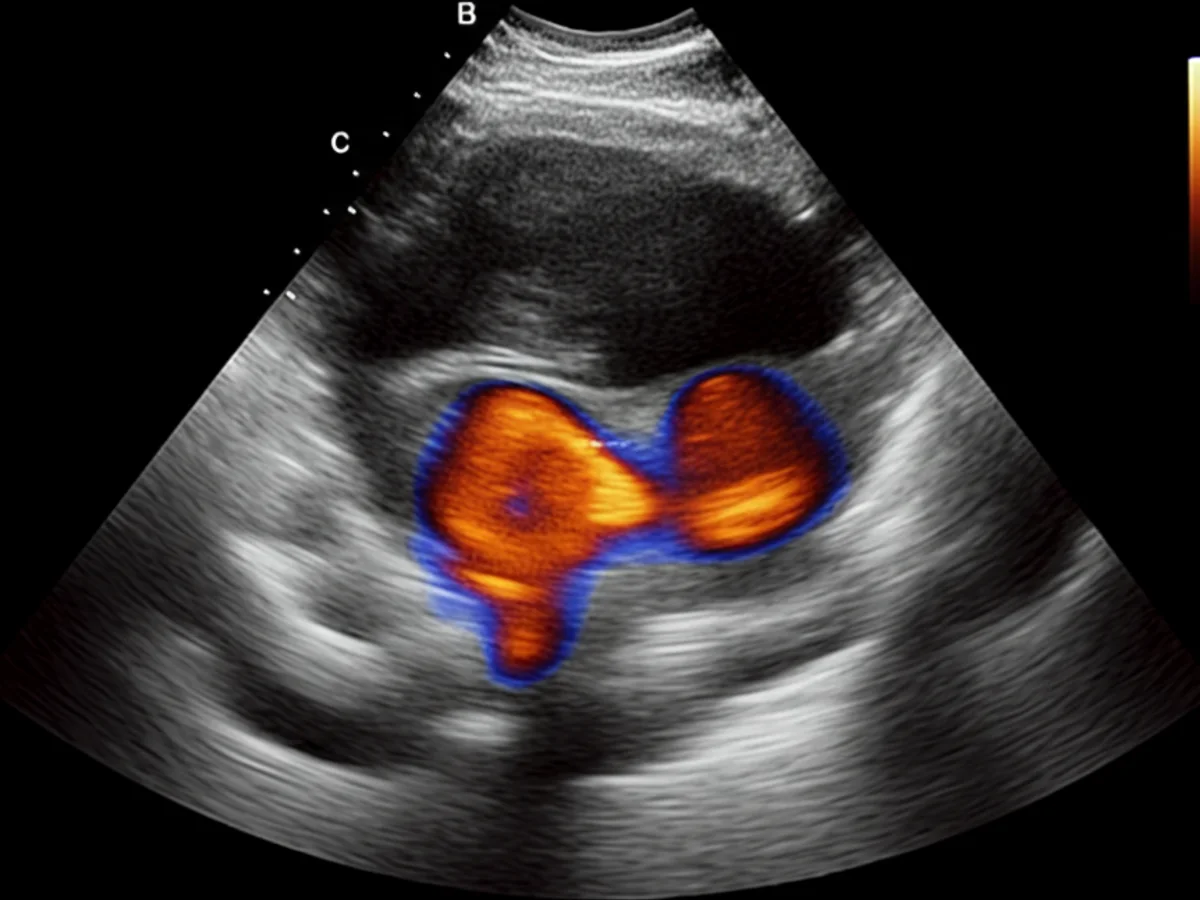

Der Tierarzt führt zunächst eine gründliche klinische Untersuchung durch, um die Beweglichkeit der Hüfte zu testen und Schmerzreaktionen zu überprüfen. Häufig kommen folgende Diagnosemethoden zum Einsatz: